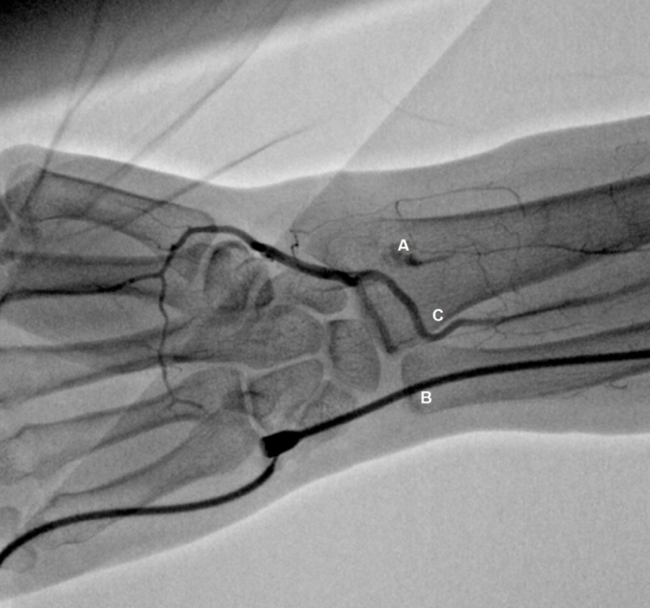

In the case of failure during insertion of the radial artery sheath by the interventionist cardiologist, changing directly to the ipsilateral ulnar artery as the second choice is viable, avoiding femoral perforation and the associated risks of bleeding. This is due to studies in which angiographs of the forearm have shown the interosseous artery’s importance in vascularization of the hand; these studies have shown that, in the case of occlusion or conditions that reduce the blood flow in the radial artery, collateral vessels of the interosseous artery were present, supplying blood to the potentially ischemic region of the hand.7,8

The indication for using transulnar access was the low amplitude or difficult to palpate radial pulse when compared to the ulnar artery (39.2%), followed by occlusion of the ipsilateral radial artery found on physical examination (33.1%) (Figure 2), spasm after attempting to puncture the radial artery (23.8%), and preservation of the radial artery for possible confection of an arteriovenous fistula in patients with chronic kidney disease (3.1%) (Table 2).

Rodrígues-Olivares evaluated the vascular anatomy of the forearm of a small sample of 14 patients submitted to transulnar approach, whose radial artery was occluded. During forearm angiography, it was evidenced that the patients presented simultaneous occlusion of the radial (chronic occlusion) and ulnar arteries (temporary occlusion due to insertion of the introducer sheath). Despite the 2 occluded arteries, no patient presented signs or symptoms of acute ischemia of the hand during the procedure, because the palmar arch was vascularized by small collaterals, all originating from the interosseous artery and leading to more than 1 region of the hand. More often, the collaterals were emitted to the radial artery, in the distal portion of the occlusion, with direct insertion to the palmar arch. After 26 months of follow-up, all patients maintained the previous ulnar pulse and no signs of hand ischemia or ulnar nerve injury were observed. These results suggest that the development of collaterals occur acutely.11